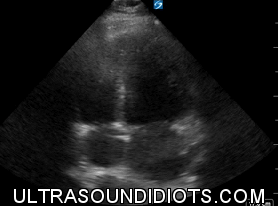

Normal Exam, Parasternal Long axis, Sector Probe.

No Effusion

Normal RVOT

Ejection Fraction is grossly normal

-Jones